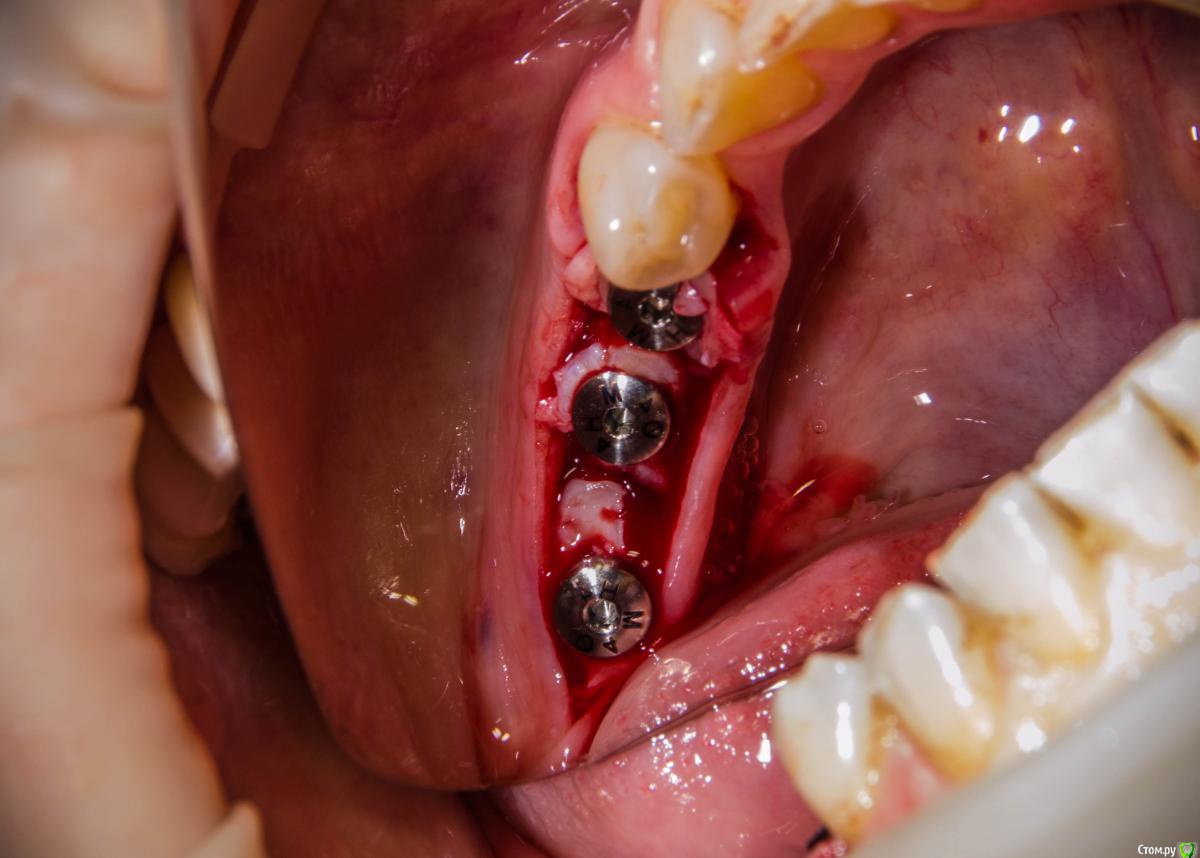

Aquarius Опубликовано 7 февраля, 2017 Поделиться Опубликовано 7 февраля, 2017 без кости? только мясо? Ссылка на комментарий

kamranchick Опубликовано 7 февраля, 2017 Автор Поделиться Опубликовано 7 февраля, 2017 без кости? только мясо?Ага Ссылка на комментарий

kamranchick Опубликовано 8 февраля, 2017 Автор Поделиться Опубликовано 8 февраля, 2017 А что и какой размер ставили?Послабляющий распил не делали?я тут не делал распилы, тут нет расщепления3,5-8,5 Ссылка на комментарий

4ebstom Опубликовано 8 февраля, 2017 Поделиться Опубликовано 8 февраля, 2017 Спасибо за публикацию.Какова ширина гребня? Ссылка на комментарий

kamranchick Опубликовано 8 февраля, 2017 Автор Поделиться Опубликовано 8 февраля, 2017 Спасибо за публикацию.Какова ширина гребня?5мм сверху в области кристального модуля имплантата дальше около 7мм) Ссылка на комментарий